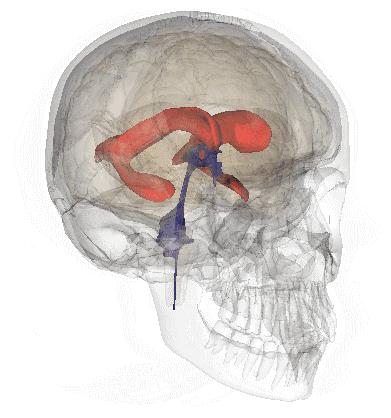

脑室系统

海马和穹窿

hippocampus:海马